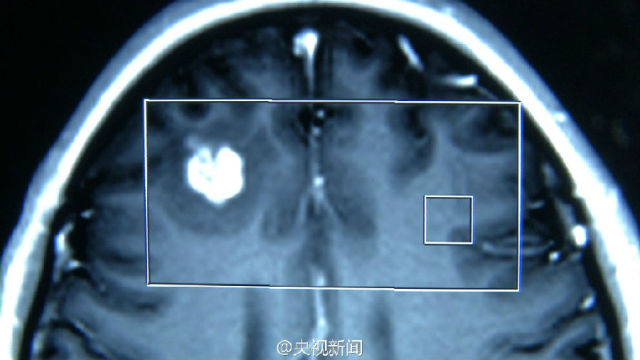

实例一:生吃动物体内长出数千虫子

苏州女孩小严半年来经常头痛、抽搐,医生开颅发现一条30厘米长白色活虫在其脑内游走!此虫是猪肉绦虫的幼虫,小严可能吃了含有绦虫卵的生蔬菜或没熟的肉类,虫卵通过消化道进入血液,再进入脑组织。医生提醒:勿食生食!食物一定要煮熟煮透再吃!(江浙佛教网提示不要食用)